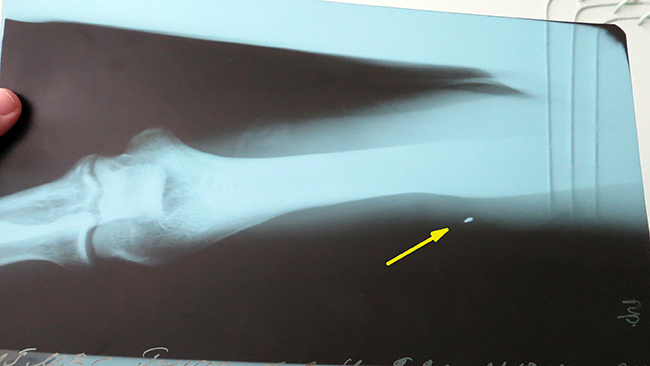

В результате взрыва гранаты за спинами милиционеров, в Сергея попало три осколка. Защитил бронежилет и шлем. Без них поражений было бы гораздо больше. А так осколки попали только в незащищенные места: поражены рука, нога и спина (осколок вошел ниже бронежилета).

– Насколько быстро мне оказали медицинскую помощь – сказать не могу, там, как-то планка времени теряется. Меня, и еще 10-15 человек, вывозили на военном автобусе. Я так понял, что это был автобус Нацгвардии. Обезболивающее еще на месте взрыва мне уколол кто-то из медперсонала военных. А в госпитале к нам сразу же вышел врач, осмотрел всех, кого привезли. Тяжелораненых сразу забрали на операцию – никто ничего не ждал. Медики работали очень оперативно. А нас уже распределили по степени тяжести. Потом: рентген, хирургия – и по палатам, – вспоминает Сергей.

– «Тяжелых» у нас нет. У всех – осколочные ранения. Сейчас в нашем отделении осталось пять человек. Еще есть раненые в нейрохирургии. Пока с осколками ничего делать нельзя. В первый период после травмы всегда есть оттек, есть воспаление. С этим мы боремся: перевязки, антибиотики. Для лечения все есть. По поводу осколков: достать его через входное отверстие практически невозможно. А он засел в массе мышц. Для того чтобы достать осколок, нужно делать большой разрез и «рыться» между мышцами. А этого, мы считаем, делать не следует. Зачастую сама операция более травматична, нежели наличие мелкого осколка. Природа устроила все так, что организм хочет «закрыть» очаг воспаления. Поэтому осколок со временем «капсулируется» – обрастает рубцовой тканью. Если не задеты ни сосуды, ни нервы, то это – не показание к операции, – разъясняет ситуацию и.о. заведующего отделением травматологии Михаил Швец. – Вообще-то, осколки могут и сами выйти. Но в данном случае осколки не круглые, а сложной формы и вряд ли выйдут самостоятельно. Но с такими осколками, полученными еще во время войны, люди и до сих пор живут.